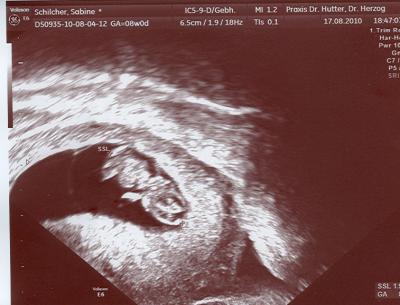

Hallo Mädels, beim US heute war alles super. Krümel ist schon fast 2 cm groß und war munter. Ärmchen u. Beinchen sind auch schon dran! Liebe Grüße und bis bald, Bine

Bild zu Alles super! - Kinderwunschbehandlung